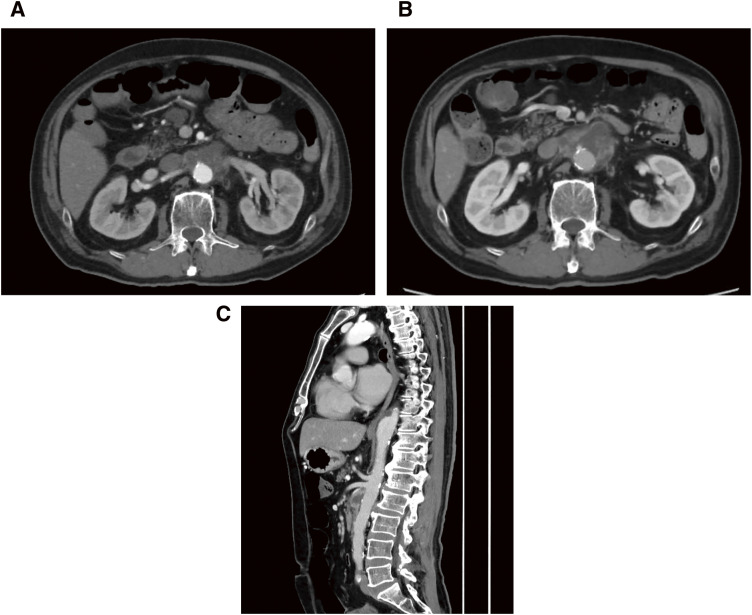

重症肌无力(MG)是一种自身免疫性神经肌肉连接障碍,很少与需要开放修复的感染性胸腹主动脉瘤(TAAA)共存。一位57岁的MG患者接受了选择性胸腹主动脉置换术。患者被诊断为MG (Osserman分类II A)。在全麻下行IV度胸腹主动脉修复术,并由全静脉麻醉维持。患者术后第5天停用呼吸机,无脊髓缺血和肌无力危象。感染性TAAA合并重症肌无力的管理不仅需要预防与危机相关的并发症,而且需要多学科的感染控制治疗。

Myasthenia gravis (MG) is an autoimmune neuromuscular junction disorder that rarely coexists with infectious thoracoabdominal aortic aneurysms (TAAA) requiring open repair. A 57-year-old patient with MG underwent elective thoracoabdominal aortic replacement. He was diagnosed with MG (Osserman classification II A). Extent IV thoracoabdominal aortic repair was performed under general anesthesia and maintained by total intravenous anesthesia. The patient was withdrawn from the ventilator on postoperative day 5 without spinal cord ischemia and myasthenic crisis. The management of infectious TAAA with myasthenia gravis warrants not only the prevention of complications associated with the crisis but also multidisciplinary treatments for infection control.